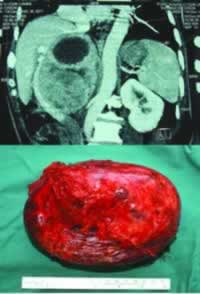

术前检查发现该患者的嗜铬细胞瘤直径已达15 cm以上,瘤体与下腔静脉、腹主动脉等重要血管及周围脏器紧紧粘连、包绕在一起(如图)。手术风险虽大,但手术过程顺利。